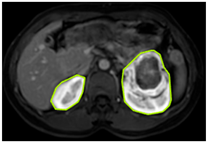

3.2.1. ROI Dataset

The images used in the study include different anatomical areas, such as the liver, spleen, and intestine. However, in order to process the data more quickly and provide more accurate results from the analysis, only the kidney areas (Regions of Interest, ROI) were extracted and evaluated. The Roboflow platform was used for spatial matching and segmentation of the kidneys. Polygonal ROI regions were defined by applying the semantic segmentation method, and then the transformations performed were verified by the radiologist, increasing the reliability of the system. In our study, MRI phase images were acquired at a resolution of 512 × 512 and the renal region of interest (ROI) was segmented and resized to 224 × 224 for input into the DenseNet architecture. In a similar study, Alhussaini et al. utilized 512 × 512 CT images and processed tumor-containing ROIs for their analysis; however, segmented region details were not provided [23]. Another study aimed to differentiate ccRCC from oncocytoma by extracting ROIs from T2-weighted images (T2-WI), pre-contrast T1-weighted images (T1-WI), and post-contrast arterial and venous phases. Tumor regions segmented at 100 × 100 mm were subsequently resized for input into the AlexNet model [24]. Unlike these studies, our approach involves segmenting the entire kidney, rather than solely the tumor region, to enable the deep learning model to leverage structural information for the organ as a whole.

Table 2 shows sample images containing ROI areas for different phases.

Table 2.

ROI areas in different phases.